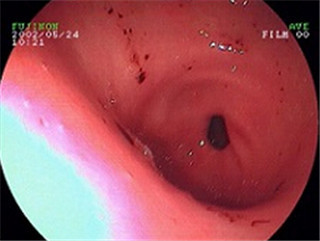

胃窦炎有哪些常见症状?阜阳胃肠医院医生说,胃窦炎是比较严重的一种胃炎疾病,跟不良饮食有很大关系,建议人们多了解其发病症状,以便及时发现病情,对症防治,早日摆脱疾病困扰。下面是阜阳兆岐肛肠医院(原阜阳中西医肛肠医院)胃肠科医生的详细介绍。

医生介绍胃窦炎的常见症状: